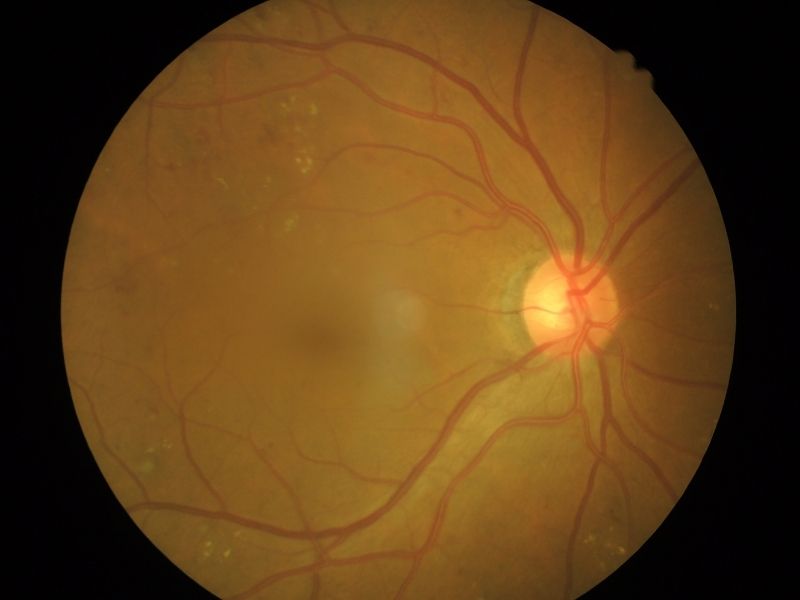

Retina yırtığı adından da anlaşılmasının mümkün olduğu üzere retinada yırtık meydana gelmesi sorunudur. Retina yırtığı genellikle, jelin çekmesinin de etkisi ile giderek büyüme eğilimde olmaktadır. Retina en başta da belirttiğimiz üzere sinir hücrelerinden oluşmaktadır ve buradaki milyonlarca hücre tarafından ışık algılanmakta ve bu algı beyne iletilmektedir. Yani beyin gibi burada da bir hücrede kalıcı hasar olduğunda yerine yeni bir hücre gelmemektedir. Bu durumda hasarlı bölge ışığı algılayamaz hale gelir ve görme kaybı yaşanır.

Hasarın, yırtığın retinanın hangi bölgesinde olduğu da belirtiler üzerinde etkili olmaktadır. Sarı nokta (makula) ışınların toplandığı merkezi bir bölge olduğu için bu anlamda çok önemli ve hassastır. Burada bir hasar olduğunda özellikle merkez görme kaybı meydana gelir. Hasta uzağı, yakını, nesnelerin merkezini iyi göremez, renk tonlarını iyi seçemez. Retinanın kenarlarında yani daha uçlarda hasar meydana gelmesi durumunda ise görme keskinlik seviyesi azalmaktadır.

Retina yırtığına acil müdahale edilmesi önemlidir. Retina yırtığı çoğunlukla uç kısımlarda meydana gelmektedir. Retina yırtığı tedavisi öncesinde detaylı bir muayene ile bütün retina taranır ve retina yırtığı tespit edilir. Yırtık tespit edildikten sonra ise genellikle tedavi için lazer tedavisine baş vurulmaktadır.